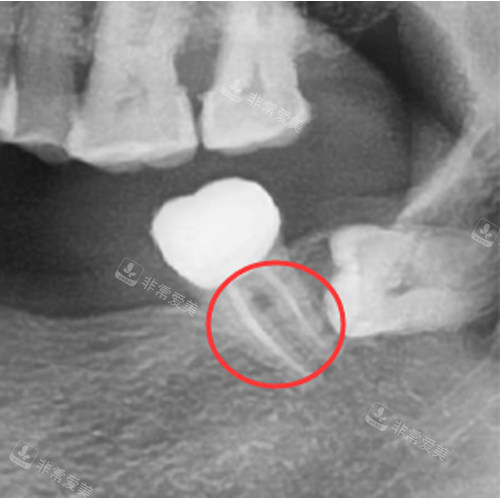

根管治疗后的牙齿

根管治疗的费用并非仅包含核心治疗步骤,术前的口腔影像检查、术中的消毒换药、术后的临时充填等环节,都会纳入整体收费。不过这些附加服务大多已包含在基础报价中,只有复杂病例需要额外增加检查或处理时,才会单独计费。

部分牙齿因龋坏重症、牙体缺损较大,治疗后需要进行嵌体或牙冠修复,这部分属于后续修复项目,不包含在根管治疗费用内,需单独计费,但这并非根管治疗本身的收费差异,而是后续保护牙齿的必要支出。

根管治疗ct照片